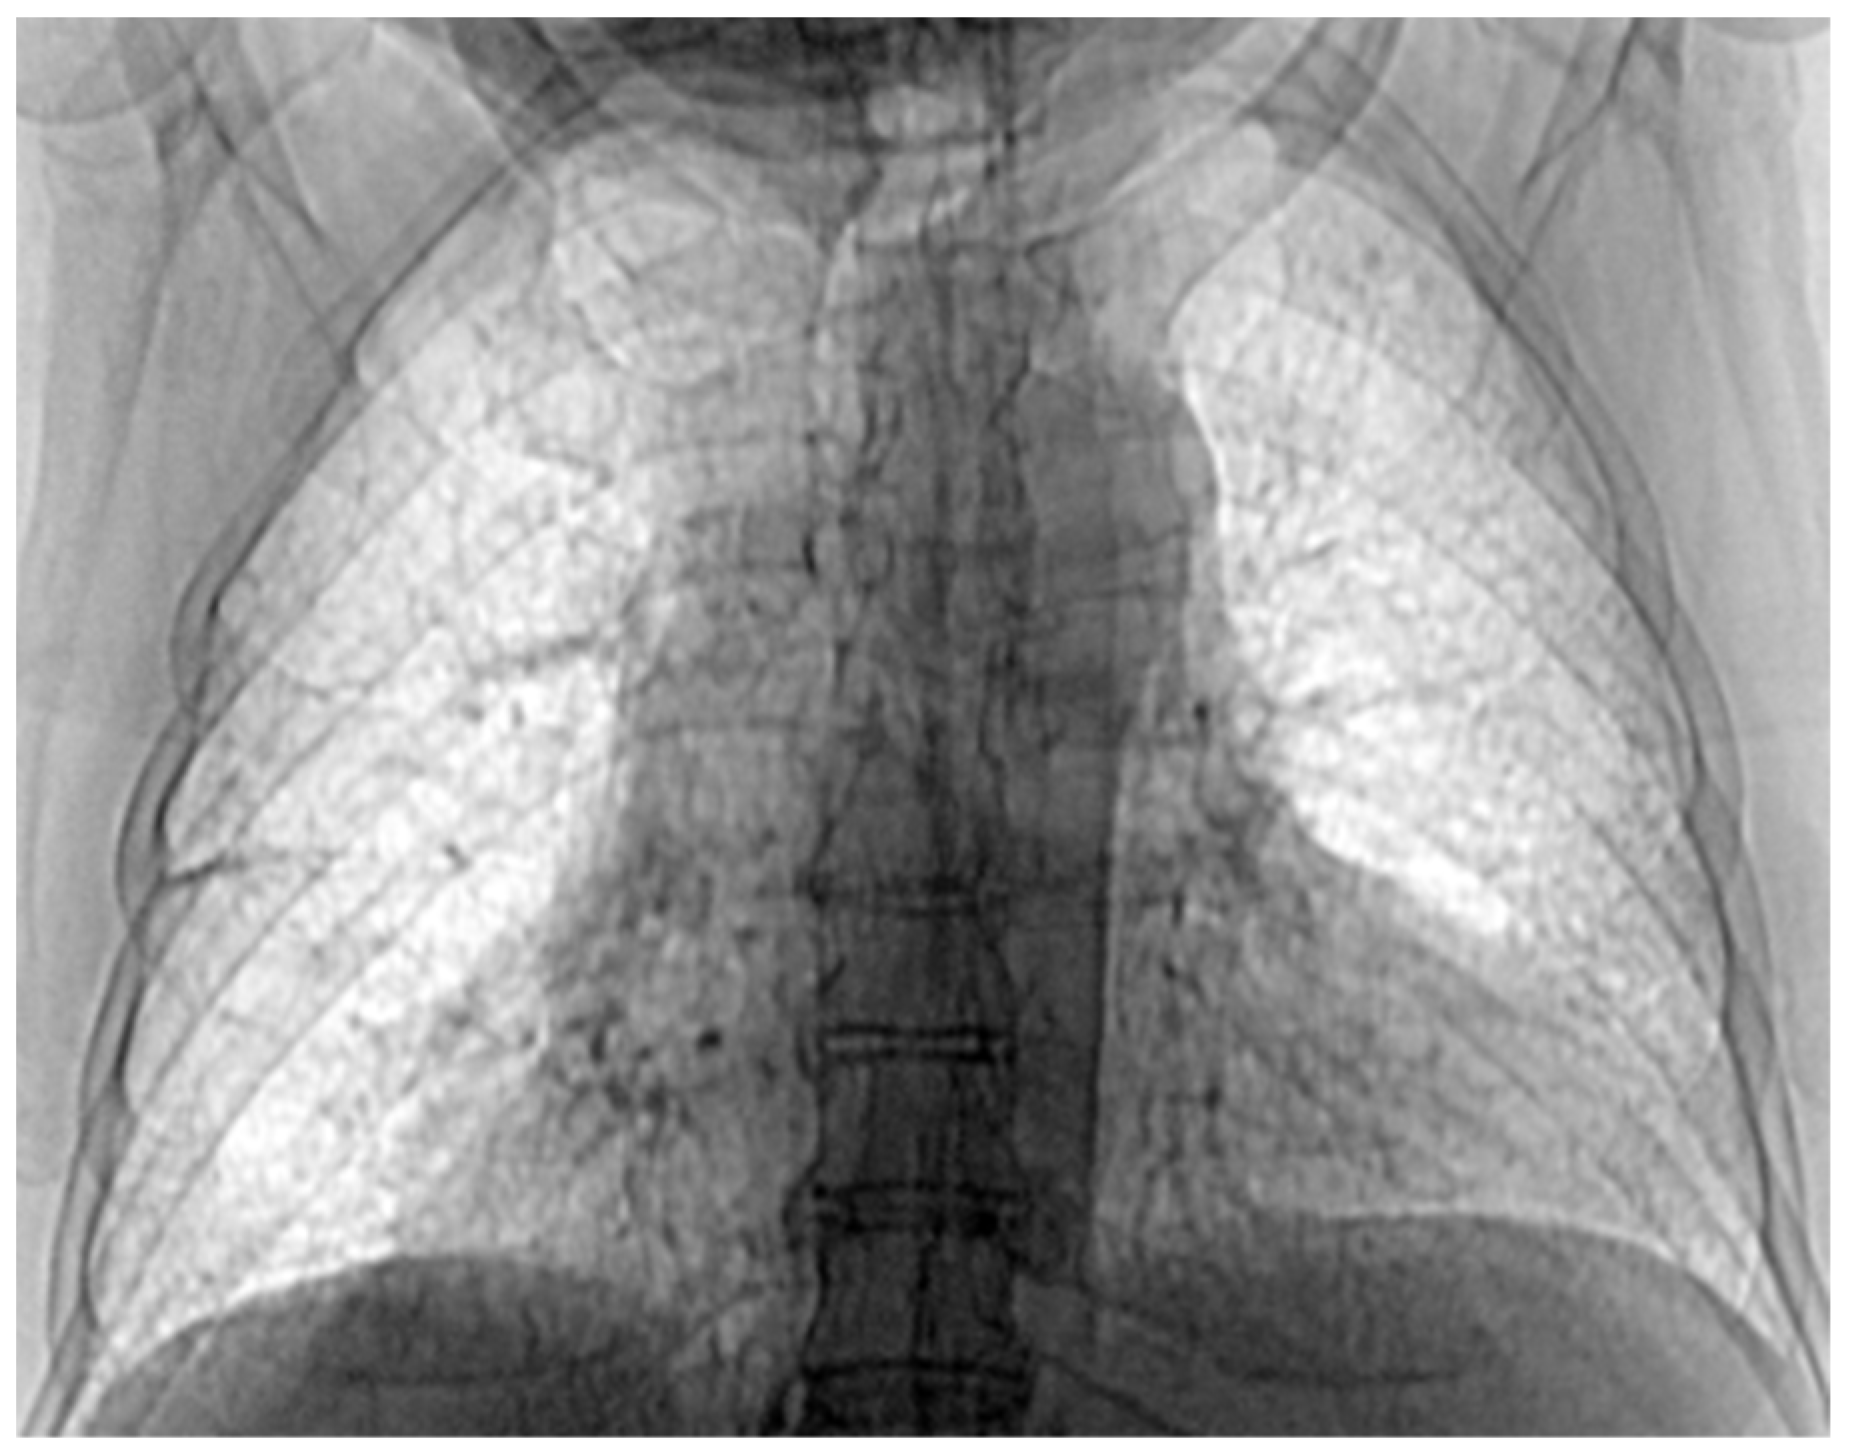

3.7. Results of Healthy Patients—A Final Comparison Using Control Data

In this subsection, we present and discuss the pulmonary CT scan of healthy lungs, which were not affected by the presence of SARS-CoV-2.

The chest radiograph of healthy lungs on which the fractal analysis was performed is shown in Figure 29a. Aside from the high-quality imaging provided by CT procedures (Figure 29a,b), the picture evaluation assured quantitative information regarding various structural features, such as the fractal dimension and lacunarity.

Figure 30 shows the 2D box-counting algorithm with the local fractal dimension calculation for the healthy-lung CT image. Figure 31 displays the 3D graphical representation of the voxels present in the CT lung image of healthy patient. Table 7 presents the calculated values for the fractal dimension and the lacunarity of the CT image evaluations for the healthy patient.

Table 7 shows the known fractal indicators, such as the fractal dimension of the CT image of the left lung, dHL = 1.6410 ± 0.3577, and lacunarity Λ = 0.0475; and the fractal dimension of the right lung, dHR = 1.6318 ± 0.3598, and lacunarity, Λ = 0.0486.

Figure 29. (a) Healthy lung image, (b) binary version, (c) mask for the left lung, (d) mask for the right lung.